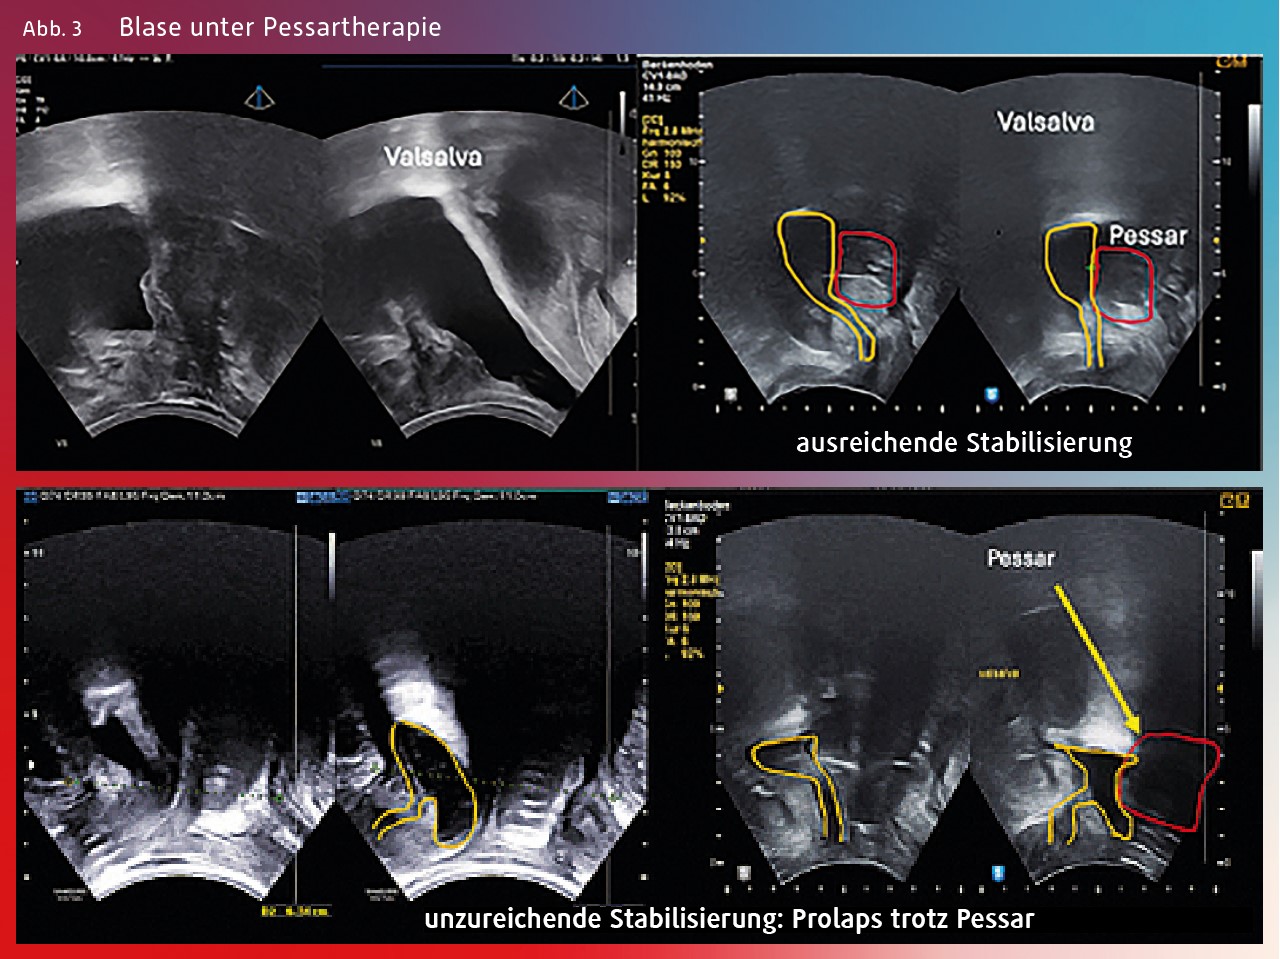

Eine Kontrolle erfolgt in 2– 6 Wochen mit liegenden Pessar, um festzustellen, ob eine Eutopie der Blase erzielt wurde. Trotz subtiler Anpassung muss in einigen Fällen dann doch ein anderes Pessar gewählt werden (Abb. 3).